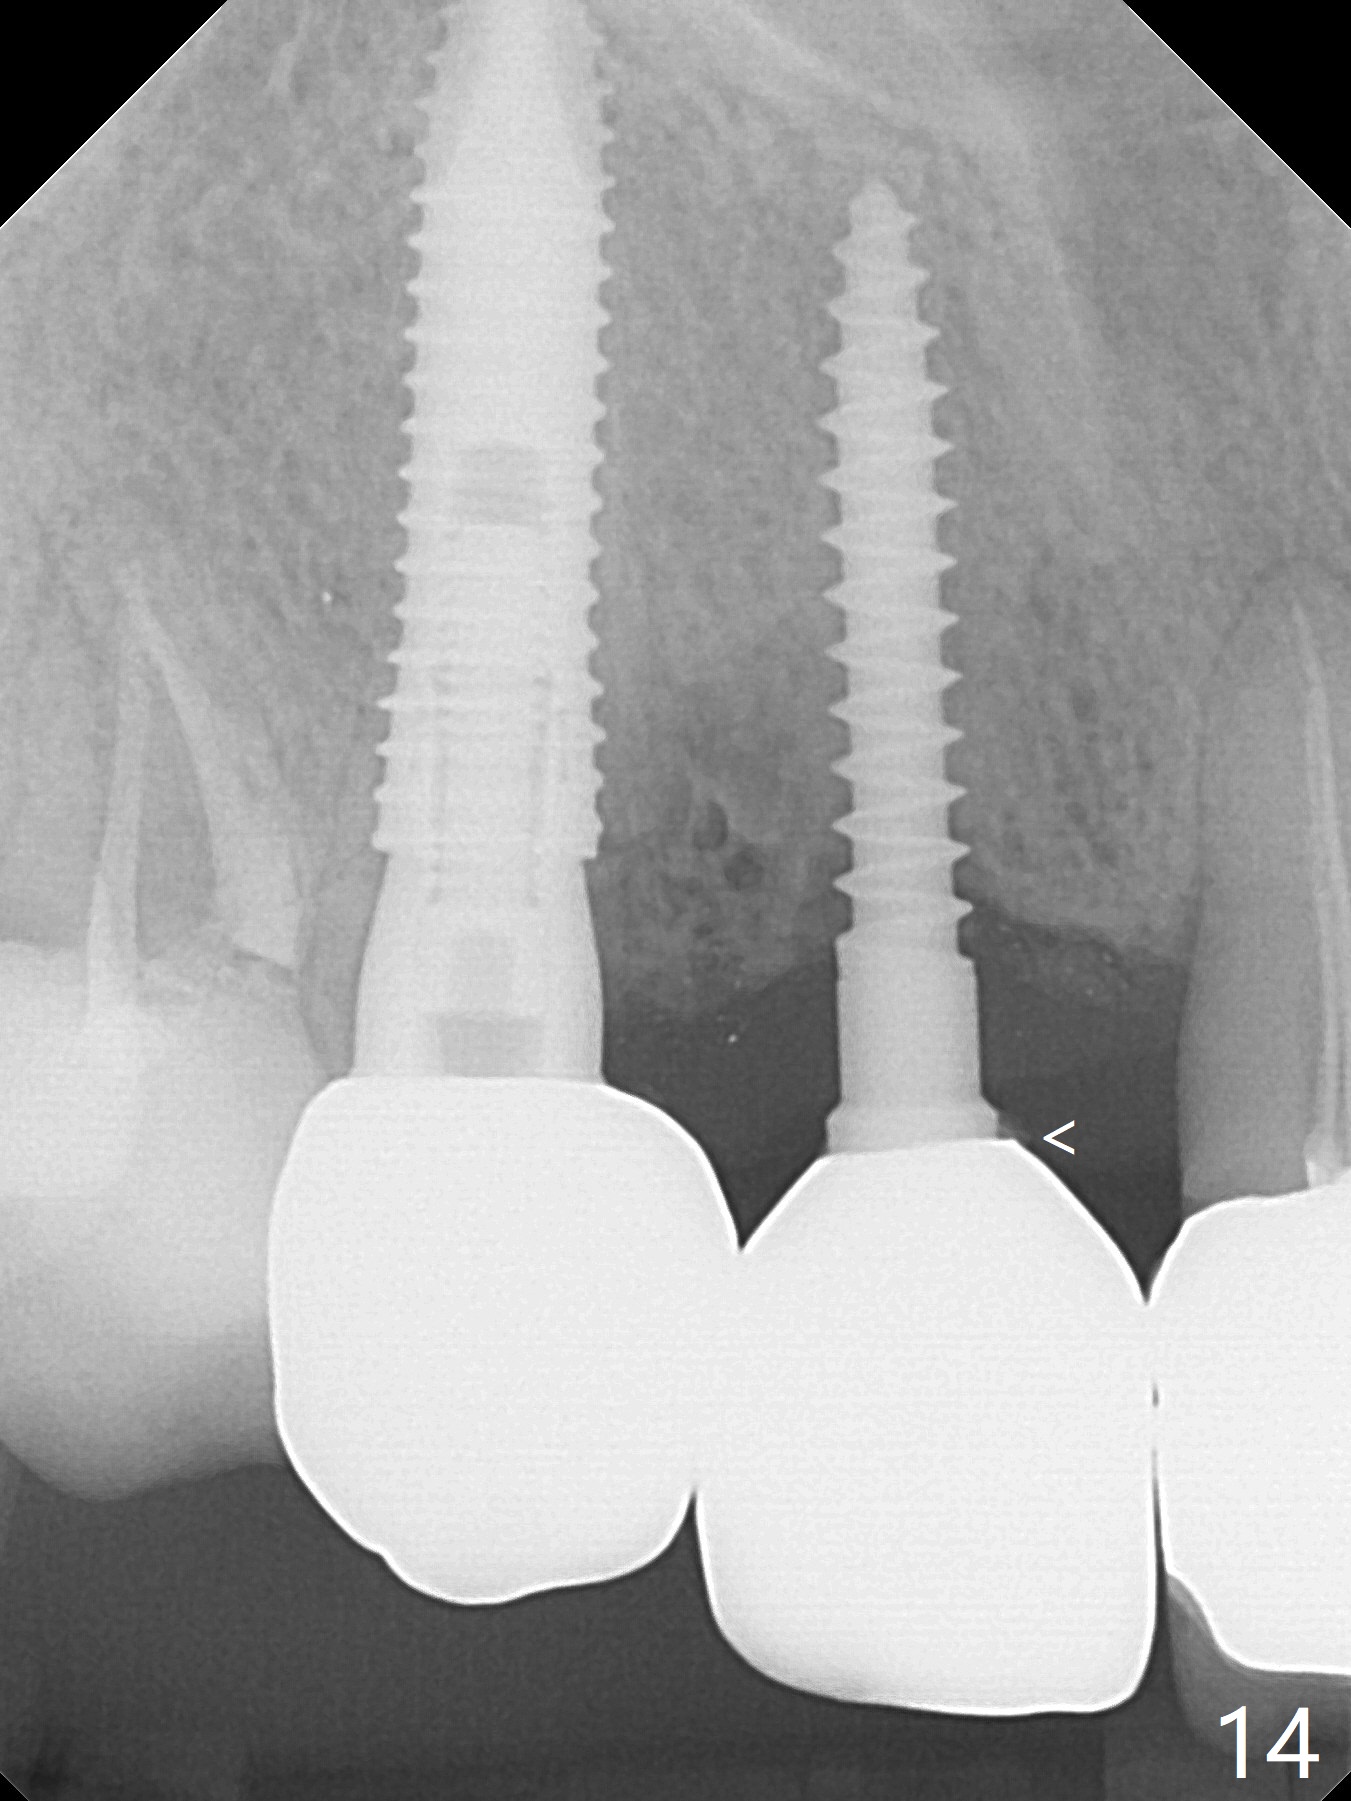

Since the ridge at #7 is ~ 4 mm, a 2.5x14 mm 1-piece implant is placed (Fig.8) after 1.2 mm (Fig.7), and 1.5 mm drills at 12 mm and 2 mm drill at 8 mm.  Later the implant is placed deeper (Fig.10).  There is no bone loss 7 or 12 months postop, respectively (Fig.11,12).  After Diode gingivectomy, there is papillary formation (Fig.13).  No provisional is provided after impression (with the abutment torqued at #6) for oral hygiene.  With access holes at #6 and 7, crowns are bonded with minimal residual cement (Fig.14 <, which is removed later).  There is no hard (Fig.15,16) or soft (Fig.17 *) atrophy 26 months postop, i.e., 13 months post cementation, due to the presence of socket shield (Fig.15 <, as compared to Fig.1).  In fact the tooth #8 has mobility and fremitus (short root/poor crown/root ratio, Fig.16); occlusal adjustment is done 13 months post cementation.  The crown is dislodged 2 years 1 month post cementation; a prefabricated post is being tried in (Fig.18).  There is no atrophy, bone loss or infection at #6 (with socket sheath (*)) or 7 two years 5 months post cementation (Fig.20-27).